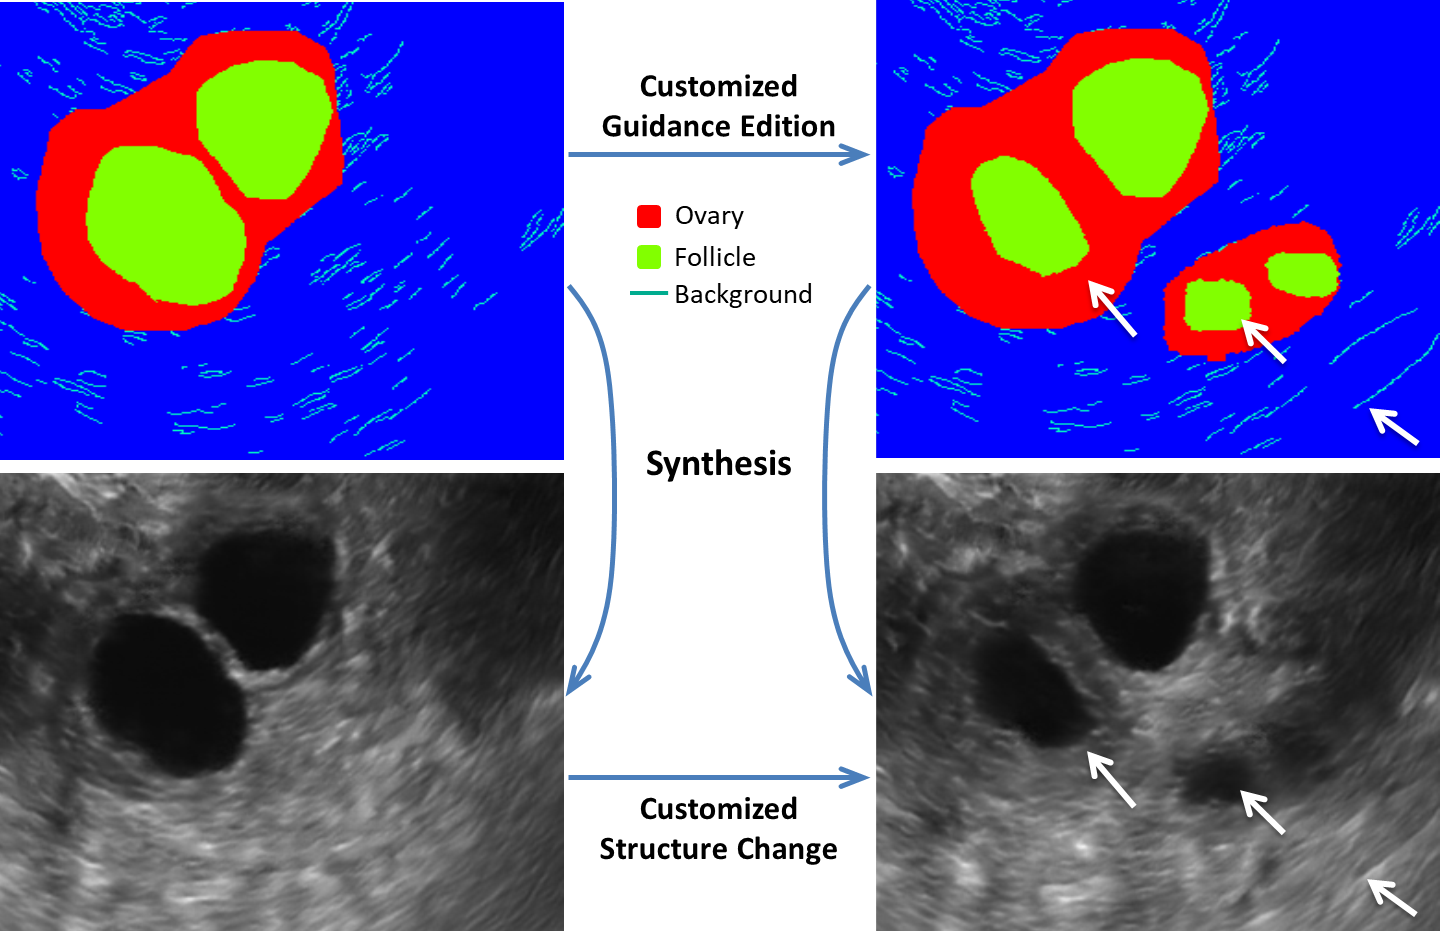

Refer to caption

Fig. 1: Three changes are edited in Canny label to synthesize a new ultrasound images. The white arrow marks the place edited. In order to make it clearer, we present Canny sketch in pseudo color.

In this paper, we devise a new end-to-end framework to efficiently synthesize realistic, high-resolution and editable US images. In order to enhance the structure fidelity and ease the synthesis, we firstly adopt a Sgan to introduce auxiliary sketch guidance upon object mask in a cGAN (Fig. 1). Sgan enables the interactive edition of fine-grained details. Although effective, Sgan is hard to generate high resolution US images. To achieve this and avoid the use of multiple cGANs, we apply a progressive training strategy [12] on Sgan to gradually generate high-resolution US images (PGSgan). By smoothly growing both the generator and discriminator with fade-in blocks (FIB) for transition, PGSgan can successfully learn to synthesize high resolution images with less training time. We validated PGSgan on ovary and follicle US image synthesis. Extensive perceptual evaluation, customized edition, user studies and segmentation tests prove the promising efficacy and efficiency of PGSgan. Our synthesized 512×\times512 images may promote the clinic training and automated analysis.

Fig. 4 visualizes the comparison of generated US images from different methods. Some defects such as background distortion (a,b), checkerboard artifacts (c) and stretching effects (d) are denoted by arrows in Fig. 4. In contrast, our method generates more realistic synthesized images. Furthermore, our method enables not only synthesizing images from real labels but also being capable to generate images using edited labels (see Fig. 5). By this way, we can create high fidelity ovarian US images with various pathological morphologies. Table 1 further lists the numerical evaluation metrics, including Freshet Inception Distance (FID) [14], Kernel Inception Distance (KID) [15] and multi-scale structural similarity (MS-SSIM) [16]. 8.5 hours was needed for training the resolution of 256 and 16 hours for resolution of 512. For testing phase, it took only 0.07s for an image generation in GPU and 5.58s in CPU on average. Our method outperformes all other compared methods with regard to all metrics, which is mainly due to the employment of auxiliary sketch and progressive training scheme.